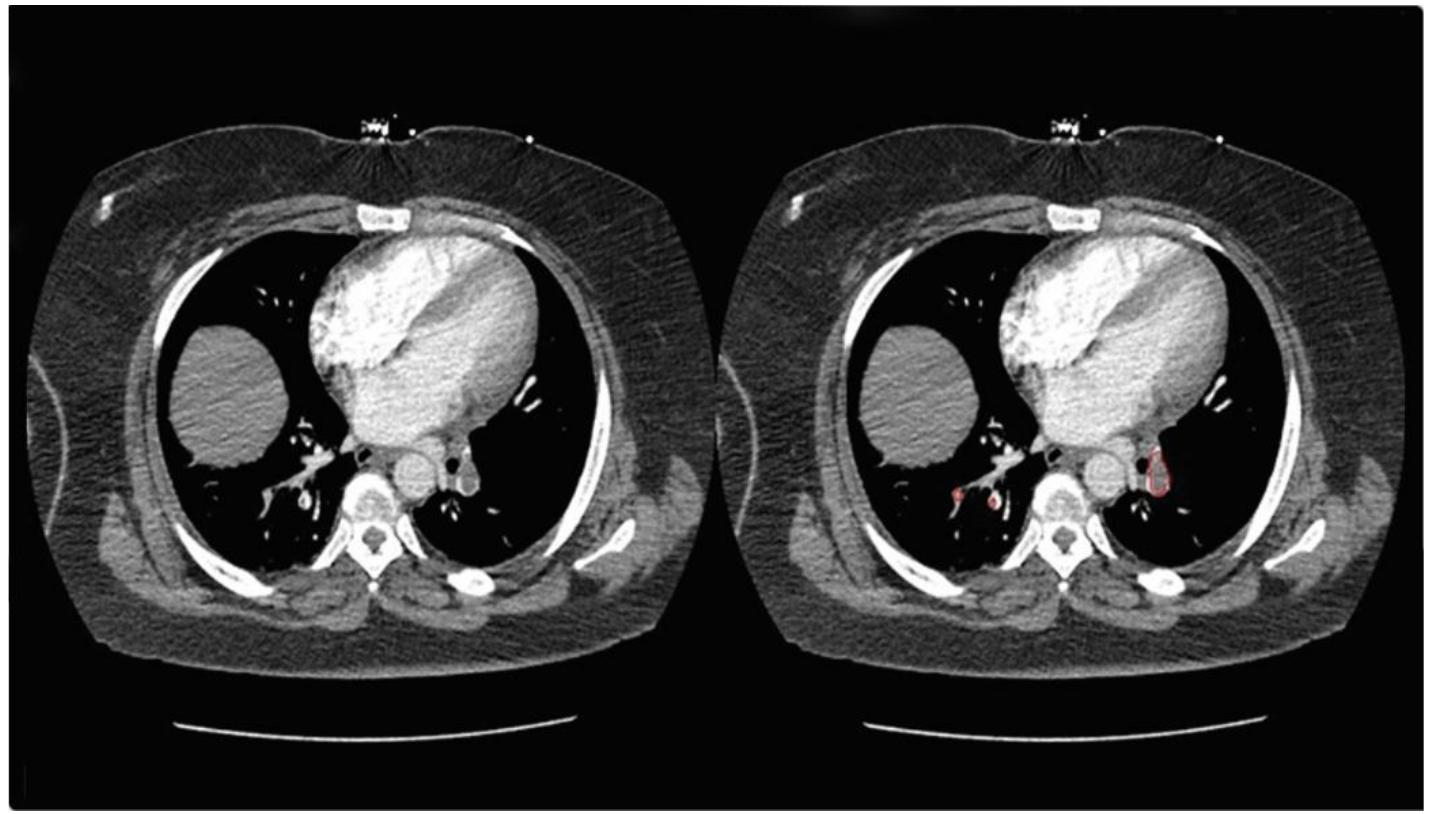

![Figure 2 « Artificial intelligence algorithm (PEAssist, TeleradTech) demonstrating bilateral pulmonary thromboembolism on th computed tomography angiogram of a patient presenting with shortness of breath in the acute setting. A number of state-of-the-art algorithms such as TeleradTech’s PEAssist [12] and Aidoc’s AI [19] solution have been of great value in emergency settings in assisting in triaging PE-positive cases for prompt treatment. Figures 1 and 2 demonstrate the results produced when using an AI TeleradTech’s PEAssist algorithm. AI has achieved a sensitivity of 80.25%, a specificity of 93.5%, and an overall accuracy of 93.3%. Figure 1 « Artificial intelligence algorithm (PEAssist, TeleradTech)- assisted analysis of computed tomography angiogram. The reference image is from healthy volunteers (true-negative case where artificial intelligence did not find pulmonary embolism).](https://figures.academia-assets.com/121472837/figure_001.jpg)